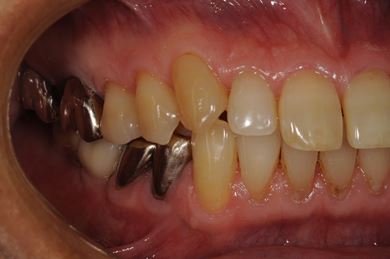

| 性別/年齢 | 男性 / 57歳 | ||||||||||||||||||||||||||||||||

| 主訴 | 右奥歯のブリッジが取れ、支柱の2本の歯が痛むため、インプラント治療を希望。 | ||||||||||||||||||||||||||||||||

| 治療内容 | インプラント2本、ハイブリッドセラミック2本 | ||||||||||||||||||||||||||||||||